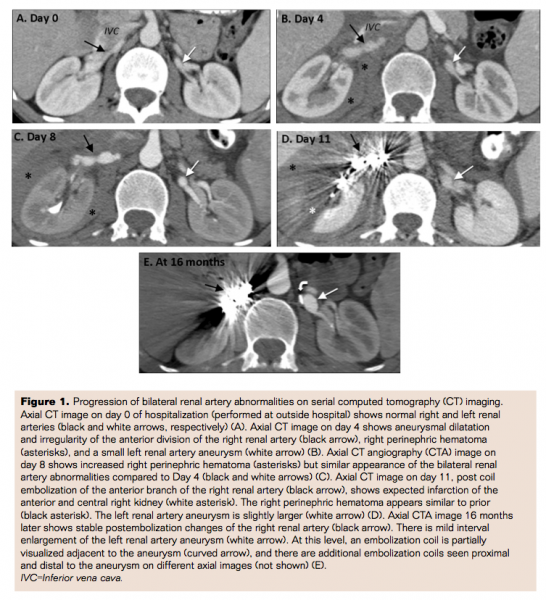

A 26-year-old white male with a history of vascular Ehlers-Danlos syndrome (EDS) presented to an outside hospital with sudden onset of right abdominal and flank pain. A contrast-enhanced computed tomography (CT) scan of the abdomen and pelvis was performed and demonstrated an infarct in the lower pole of the right kidney. Of note, the renal arteries and hepatic arteries appeared grossly normal (Figures 1 and 2). The patient was then transferred to our institution for further management.

On day 4 of hospitalization, the patient experienced severe exacerbation of his abdominal pain. A CT of the abdomen was performed and revealed new aneurysmal dilatation of the anterior division of the right renal artery, a right perinephric hematoma, and a small left renal artery aneurysm (Figure 1B). The right lower pole renal infarct was grossly unchanged. There was also mild dilatation of the left and right hepatic artery branches (Figure 2B). In spite of these CT findings, the clinical service elected to continue conservative management with adequate pain control and the patient remained hemodynamically stable.

On day 8 of hospitalization, CT angiography (CTA) was performed for imaging follow-up and demonstrated increasing right perinephric hematoma and grossly similar appearance of the bilateral renal artery abnormalities (Figure 1C). There was, however, a new large saccular aneurysm involving the terminal branch of the anterior division of the right renal artery, which had developed since day 4 (Figures 3A and 3B). There was subtle contour irregularity of the aneurysm, suggestive of aneurysm rupture. In addition, CTA showed new fusiform aneurysms of the left and right hepatic artery branches (Fig 2 C). Because of the newly developed saccular aneurysm and the increased perinephric hematoma, Interventional Radiology (IR) was consulted for emergent coil embolization of the aneurysm.

However, immediately following the CTA study, the patient became severely hypotensive, with systolic blood pressure in the 60s, and with a drop in hemoglobin from 11.7 to 6.3 g/dL. He was transferred to the ICU and resuscitated. Once stabilized, the patient was taken to the interventional radiology suite for coil embolization of the large right renal artery aneurysm, felt to be the source of significant bleeding.

On day 11 of hospitalization, a CT abdomen and pelvis was performed for persistent abdominal pain and a tense, distended abdomen. The CT scan showed large volume hemoperitoneum, without evidence of active bleeding. As expected, there was evolving infarction of the majority of the anterior and central right kidney status post embolization (Figure 1D). The hepatic artery aneurysms had also increased in size (Figure 2D). General surgery was consulted and the patient underwent exploratory laparotomy with evacuation of two liters of hemoperitoneum. The postoperative course was uneventful and the patient was eventually discharged from the hospital in good condition.

The patient was lost to follow-up at our institution. However, 16 months later, he presented to our emergency department with symptoms of chest pain. A CTA of the chest was performed and demonstrated right lower lobe airspace consolidation. Interestingly, the previously seen right hepatic artery aneurysm was no longer visible at the same anatomic level as on prior scans, despite good visualization of other hepatic artery branches in the right hepatic lobe. The left hepatic artery branch was faintly seen and normal in caliber (Figure 2E). These findings illustrated spontaneous regression of the hepatic artery aneurysms. Per medical records, there was no interval therapy for these lesions. However, this CTA also showed evidence of several metallic coils in the left renal artery branches, proximal and distal to the existing left renal artery aneurysm. The aneurysm was still perfused and appeared slightly larger since prior scan (Figure 1E). There were no perfusion defects in the left kidney. Thus, the coil packing was insufficient for vessel occlusion. There was brief documentation that the patient had undergone therapy for the left renal artery aneurysm at an outside institution, though the date and details of the procedure (e.g., whether emergent or elective) were not provided.